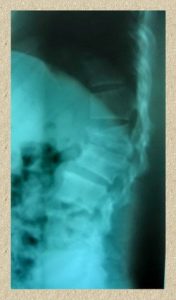

脊椎・関節治療センター 人間の一生のうちは関節や背中に強い痛みが起こることが少なくとも1回くらいはあるでしょう。早期にきちんと受診し適切な初期治療を受けることが非常に重量です。なぜかというと、適切な治療を受けずに放置しておくと、痛みの範囲が広がったりとどんどん悪循環になり、ようやく手術に進むからです。Bangkok Spine and Joint Centerは、骨・脊椎疾患の総合予防治療センターです。以下の3つの治療法と1つの予防法があります。

3. Surgical Treatment

脊椎手術において低侵襲手術を施行しています。皮膚の切る範囲を減らし、術後の回復を著しく早めています。治療法の代表例としては次のようなものがあります。